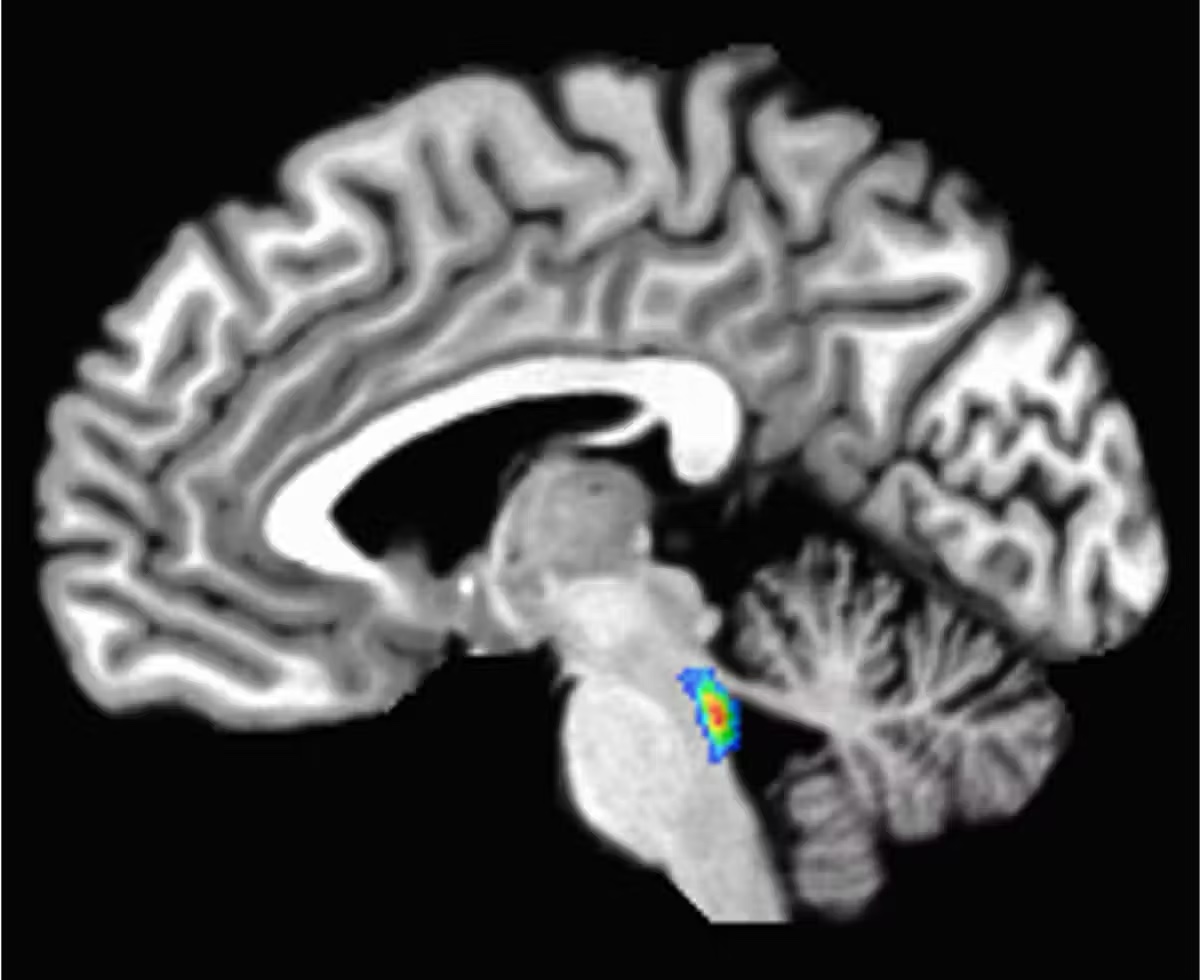

In the earliest of these changes, a tangled version of a protein called tau starts building up in a tiny region deep in the brain involved in sleep, attention and alertness, called the locus coeruleus. Tau later spreads to the rest of the brain.

Developing tau tangles doesn’t mean a person has Alzheimer’s disease – in fact, it happens to nearly everyone to varying degrees. But because these changes start in the locus coeruleus, some brain researchers – myself included – see this area as a canary in the coal mine for developing Alzheimer’s disease.

The locus coeruleus sits in the brain stem, the lowest part of the brain. Its name, “blue spot,” comes from a pigment called neuromelanin that its cells produce.